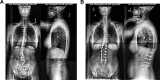

Results: A total of 350 patients were identified: 173 OPEN patients and 177 MIS. OPEN patients were significantly younger than MIS patients (61.5 years vs 63.74 years, P = .013). The OPEN group had significantly more females (87% vs 76%, P = .006), but both groups had similar body mass index. Preoperative lumbar Cobb was significantly higher for the OPEN group (34.2°) than for the MIS group (26.0°, P < .001). The mean preoperative Oswestry Disability Index was significantly higher in the MIS group (44.8 in OPEN patients and 49.8 in MIS patients, P < .011). The preoperative Numerical Rating Scale value for back pain was 7.2 in the OPEN group and 6.8 in the MIS group preoperatively, P = .100.

Conclusions: Patients chosen for MIS for ASD are slightly older and have smaller coronal deformities than those chosen for open techniques, but they did not have a substantially lesser degree of sagittal malalignment. MIS surgery was most frequently utilized for patients with an sagittal vertical axis under 6 cm and a baseline pelvic incidence and lumbar lordosis mismatch under 30°.